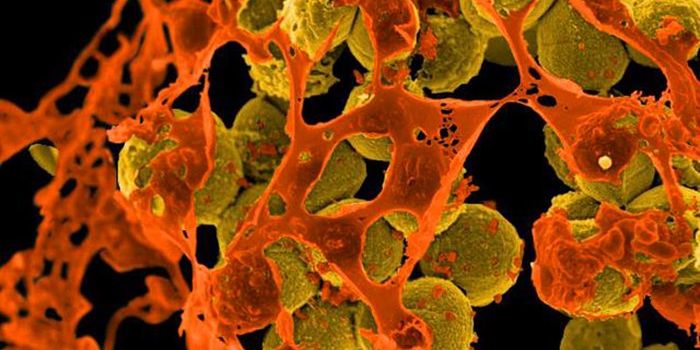

AUG 20, 2016Clinical & Molecular DXCan the staph superbug, also known as MRSA, be brought down by salt? Scientists finally expose a key weakness in these b ...